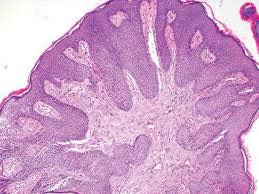

Condylomata acminatum or venereal warts (commonly an HPV 6 genesis) develop in the vicinity of the anus, vulva, glans penis and mucosal membranes such as the oral cavity. Focal epidermal hyperplasia is substantiated by hyperkeratosis, parakeratosis, varying or extensive acanthosis and papillomatosis. Trichilemmal type of keratinisation may emerge (13) . Vacuolated cells may be visualized in the upper malphigian layer in the early lesions. Atypical cells, characterized by abundant, eosinophilic cytoplasmic accumulations may be demonstrated. Miniature vacuolated cells and pyknotic nuclei are exhibited in the thick, basal stratum corneum (13) . Ancient verrucae may emerge as papillomas or keratosis. Flat warts with involution display a degenerative epidermis and a prominent mononuclear dermal or intra-epidermal inflammation. The viral nuclear inclusions are basophilic. They can be established with immunohistochemistry and in-situ hybridization procedures. The eosinophilic aggregates in the cytoplasm are indicative of aggregated tonofilaments. In concordance with the HPV induced lesions, benign or malignant skin tumours or tumour like conditions manifest, such as seborrheic keratosis, bowen's disease, invasive squamous cell carcinoma and epidermodysplasia verruciformis. The keratinocytes reveal altered keratin on account of the viral infection and further alterations ensue with malignant conversion. A biopsy may be contemplated with ambiguous lesions, in the patients refractory to therapy, in immune-deficient individuals, with extensive lesions or lesions which elucidate atypical components. A routine biopsy can be advocated to investigate a dysplasia.